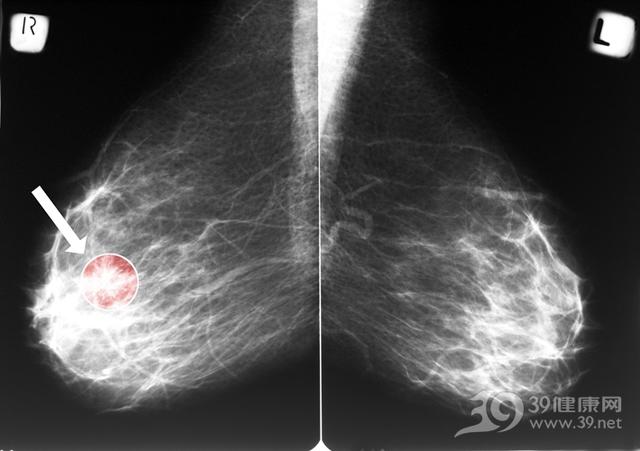

“早期乳腺癌”,是指癌肿生长处于组织学或临床的早期阶段,未侵犯基底膜,所以也称“原位癌”或“非浸润性癌”.早期乳腺癌,包括导管内癌和小叶原位癌.导管内癌或称为导管内原位癌,是指癌瘤局限于导管内,未突破管壁基底膜的非浸润性癌.少数病人可有刺痛或不适感,还有部分病例可能触不到肿块.小叶原位癌,是指癌细胞在乳腺小叶小管基底膜内,呈膨胀性生长阶段.多发生于绝经前期的中年女性,年龄在42~46岁,癌灶体积小,可以分散存在.临床检查多触不到乳内肿块,因此往往被误诊为乳腺小叶增生.乳腺癌吃什么,早期乳腺癌治疗以手术为主,手术方式可选择全乳切除术.早期乳腺癌治疗后预后较好,10年生存率可达95%以上.因此早期发现,早期诊断,早期治疗是提高乳腺癌患者生存率的有效方法之一.